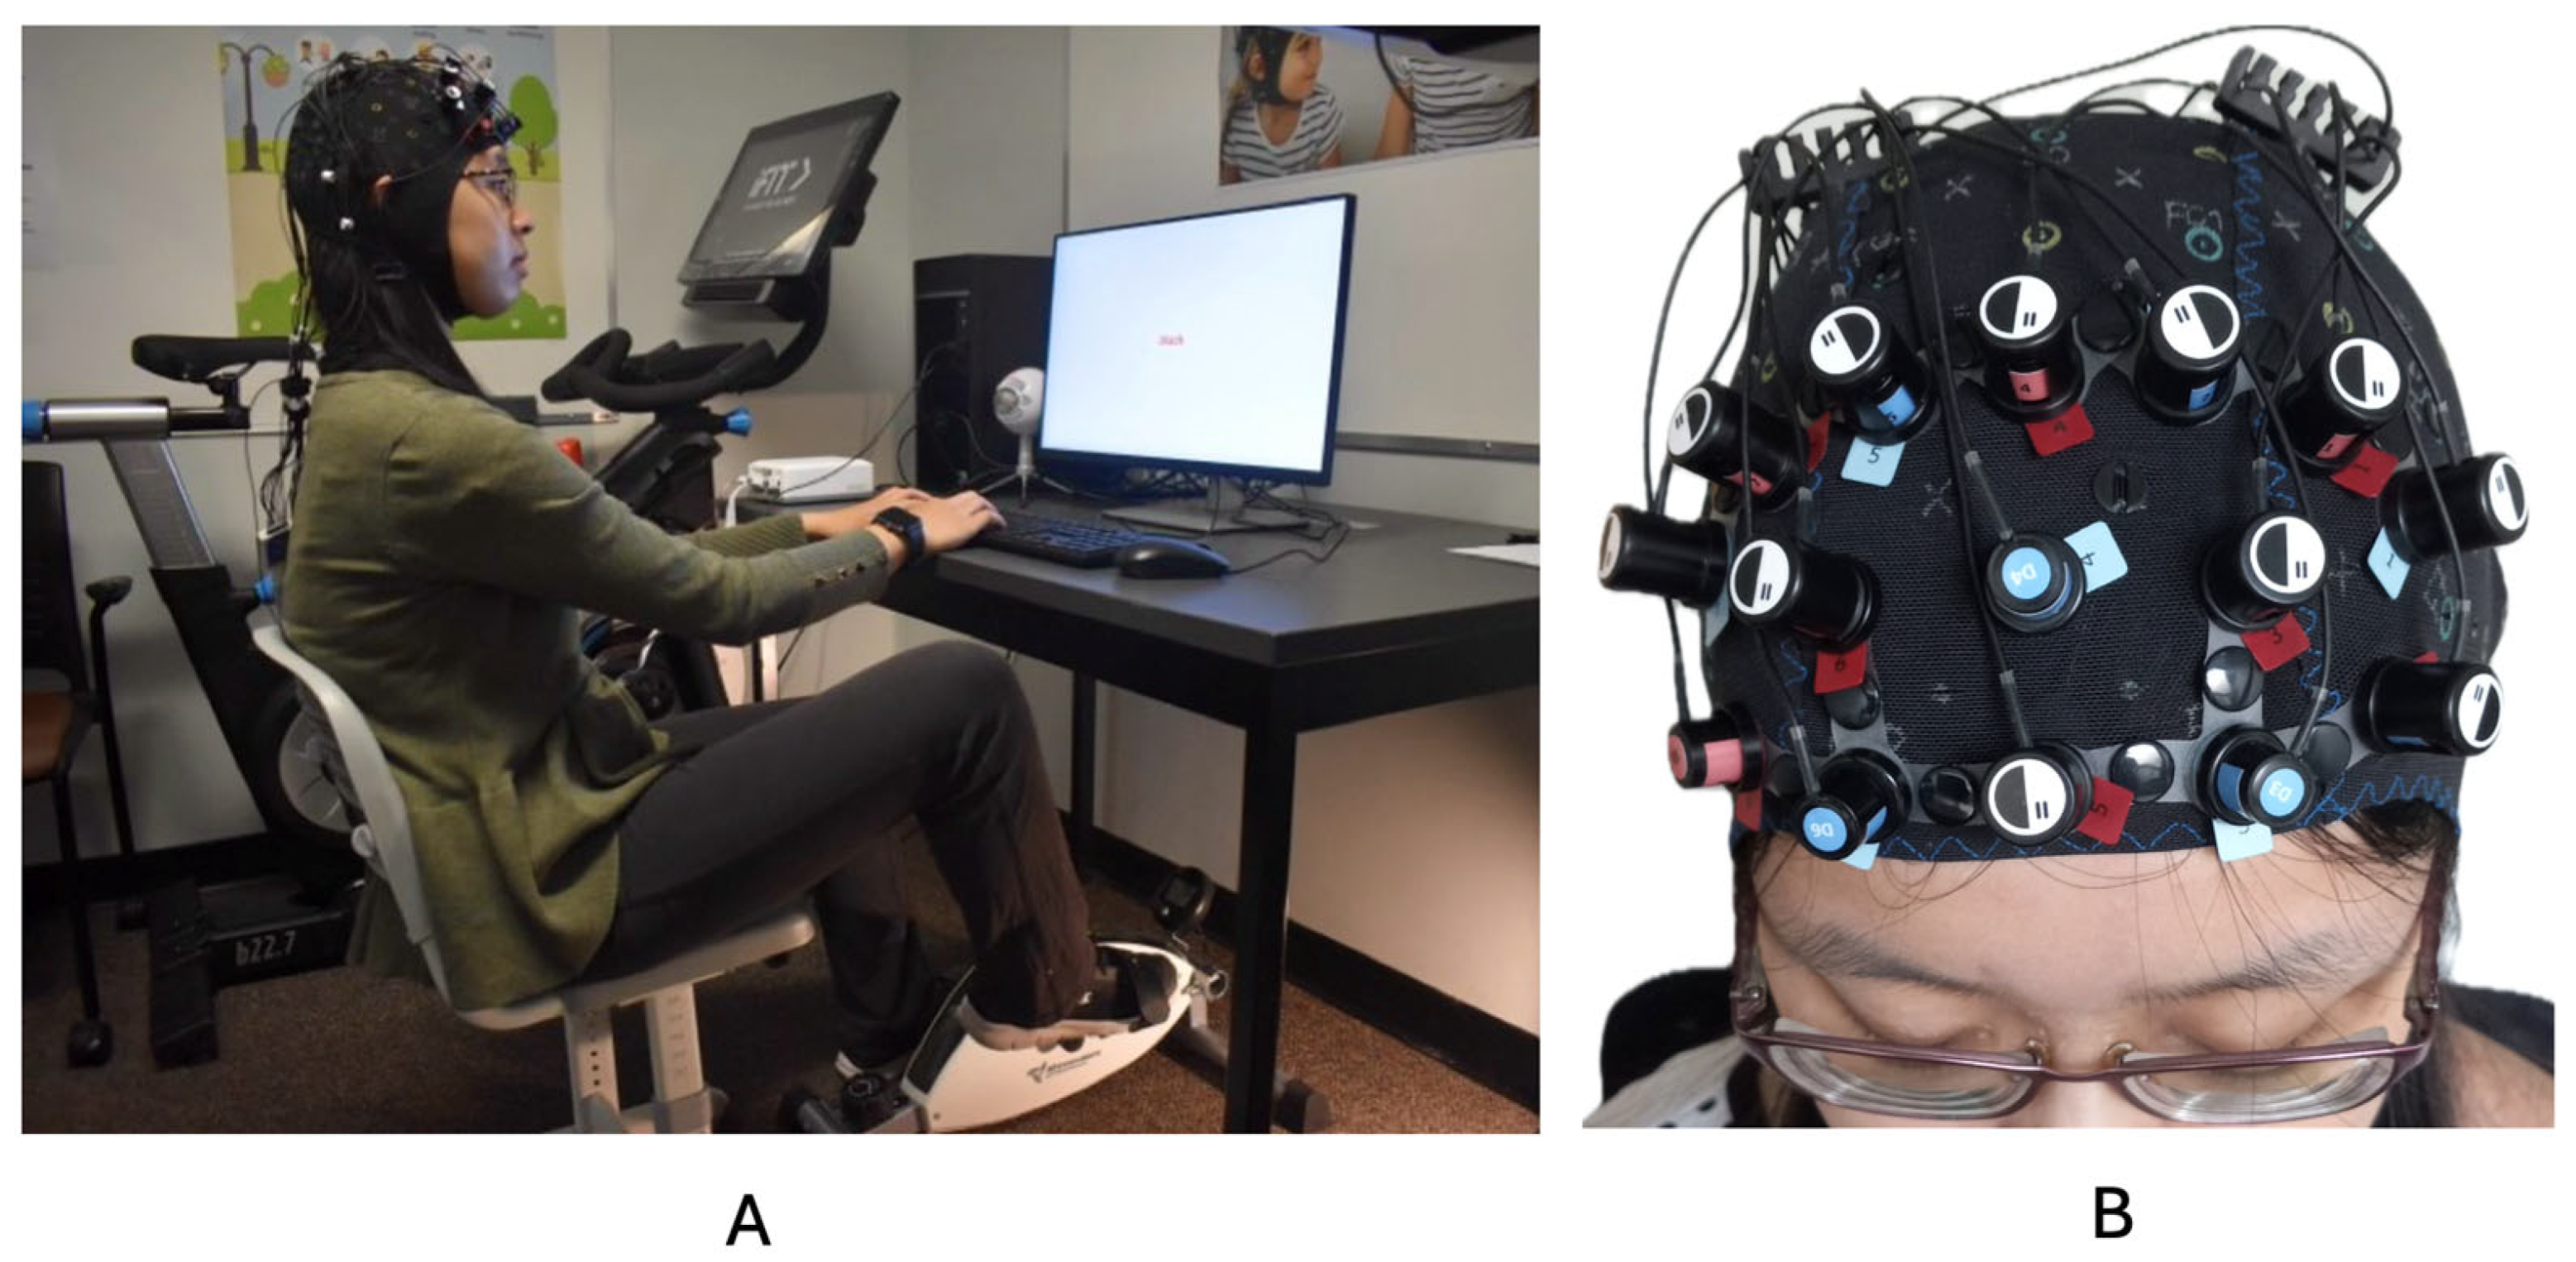

2.2.6. Left DLPFC Activity Using Functional Near-Infrared Spectroscopy (fNIRS)

Movement Condition

Stationary Condition

Procedure